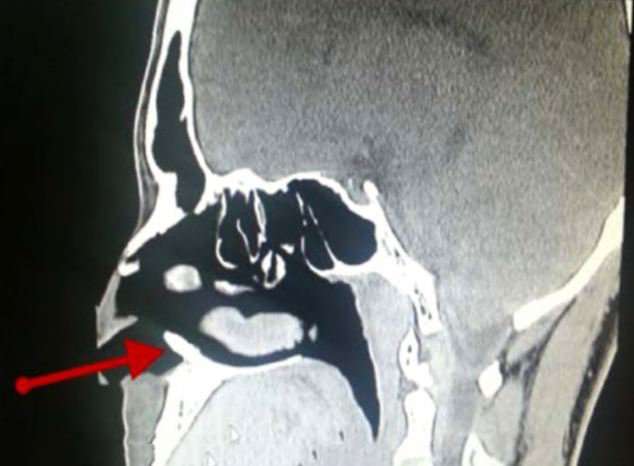

Երեք տարի շարունակ ամսական մի քանի անգամ կրկնվող քթային արյունահոսությունները ստիպել են Սաուդյան Արաբիայի 22-ամյա բնակչին դիմել բժիշկների, որոնք նրա քթի մեջ հայտնաբերել են մոտ 1 սմ երկարությամբ սպիտակ ոսկրային զանգված։

Անսպասելի գտածոյից հետո օտոլարինգոլոգը որոշել է խորհրդակցել ատամնաբույժի հետ, որը եզրակացրել է, որ անհայտ զանգվածը լրացուցիչ ատամ է, որն անհասկանալի պատճառով աճել է երիտասարդի քթի մեջ։